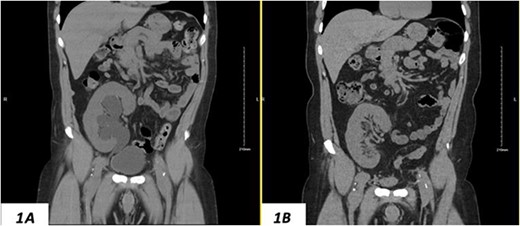

Despite a new onset proteinuria of 50 mg/dl, he continued to have a good functioning graft with a creatinine level of 93 μmol/l corresponding to an estimated glomerular filtration rate (eGFR) of 78 ml/min/1.73 m2. Nonetheless, he had also been noting an inguinal bugle that becomes more prominent as the day progressed, and it regressed at night. Upon further investigations, an ultrasound of the allograft revealed moderate-to-severe hydronephrosis. Further imaging using computed tomography scan (CT) confirmed the presence of upstream moderate hydronephrosis (Figs 1A and2A) along with a reported herniation of the ureter in a right inguinal hernia, resulting in a focal distal ureteric dilatation of 3.5 cm (Fig. 3A).

(A) Hydronephrosis of the allograft ureter on preoperative coronal CT scan; (B) significant improvement of hydronephrosis on the 10-month postoperative image.